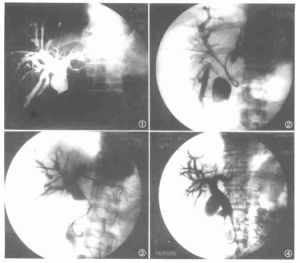

慢性膽管炎B超膽道顯影特徵為:①病變部位膽管呈不規則的多發性狹窄,而膽管黏膜表面光滑;②狹窄病變呈局限性或瀰漫性,也可呈節段性改變;③狹窄膽管近端輕度擴張;④病變累及肝內膽管時,可見肝內膽管分支減少,僵硬變細似枯樹枝狀或串珠狀、半球狀擴張,內徑2~3mm。約80%病例肝內、外膽管同時受累,20%僅累及肝外膽管,膽總管(CBD)內徑小於4mm,壁顯著增厚,膽系無結石和腫瘤徵象。膽囊受累時則膽囊壁厚,功能減退或消失。當膽道造影證明存在肝內或肝外膽管狹窄,診斷即可成立,故典型的放射學改變被確認是診斷的金標準。